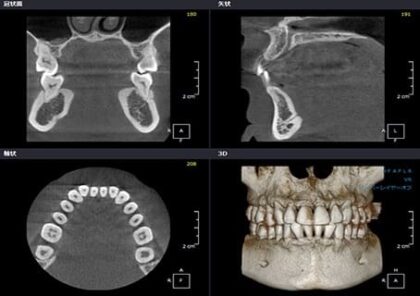

CTスキャン:三次元で撮影できる精度の高い検査方法ですが、虫歯診断ではなく、インプラント治療や外科手術前の診断に使われることが多いです。